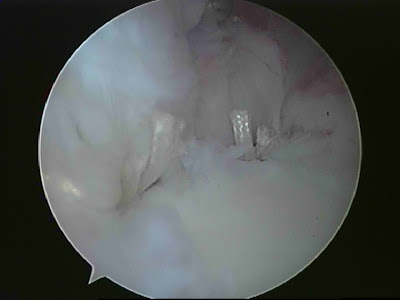

Arthroscopic picture showing Hill Sachs lesion

Picture above showing Labral detachment